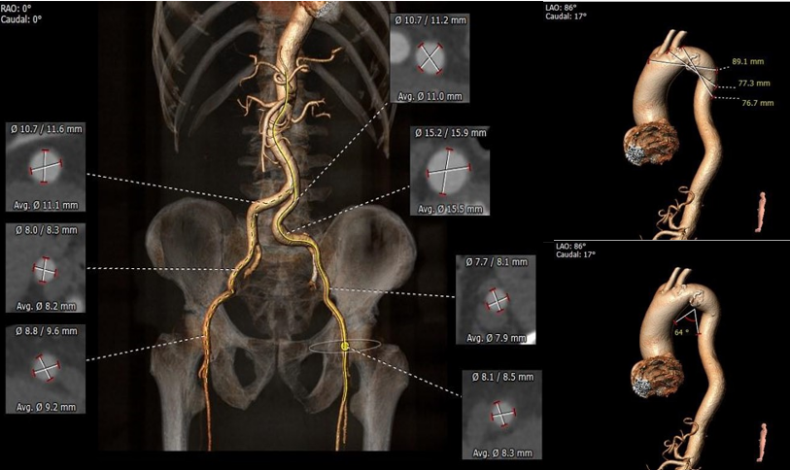

5. 双侧髂动脉扭曲,左髂总局部扩张,股动脉穿刺区域未见钙化斑块,股动脉直径良好 。

外周血管及主动脉弓解剖:

2. 根据当前影像资料及测量数值,计算跨瓣角度为 RAO 10° CAU16°(双窦展开)左右。

3. 使用23mm 球囊预扩,预扩角度 RAO 10° CAU16° (双窦展开),预装 AV29 瓣膜。

4. 瓣膜释放角度RAO 10° CAU16° (双窦展开),瓣环下2mm左右释放,瓣膜释放至工作位后调整至LAO 5° CRA 35°左右评估瓣膜展开形态及稳定性。